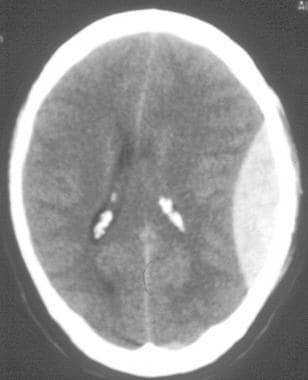

Intracranial Pressures and Brain Bleeds

Intracranial pressures and brain bleeds.